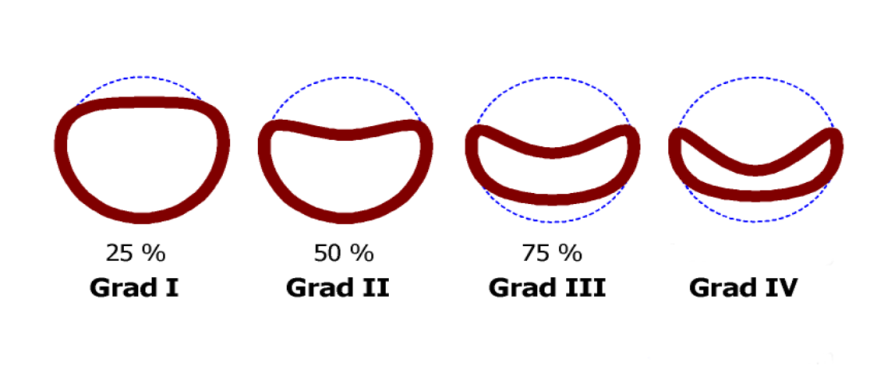

После проведения всех исследований определяется степень поражения трахеи и определяется тактика лечения.

В серьезных случаях, например, при сужении трахеи от ее просвета на 50% и более, собаке показано только хирургическое лечение коллапса трахеи (операция).

Схематическое изображение степени колапса трахеи